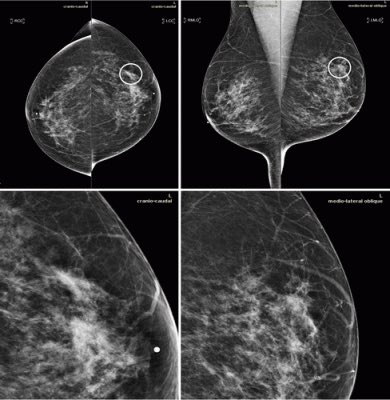

-كما يفضل التردد لنفس المركز الذي تم اجراء الفحص فيه سابقا حيث من المهم مقارنة الفحص الحالي بالسابق والبحث عن اي تغيرات جديده في الاشعه قد تشير الى الظهور المبكر للمرض والتي غالبا ما تكون صغيرة لاتتجاوز حبة الارز ( شاهد العلامة في الصورة المرفقة)